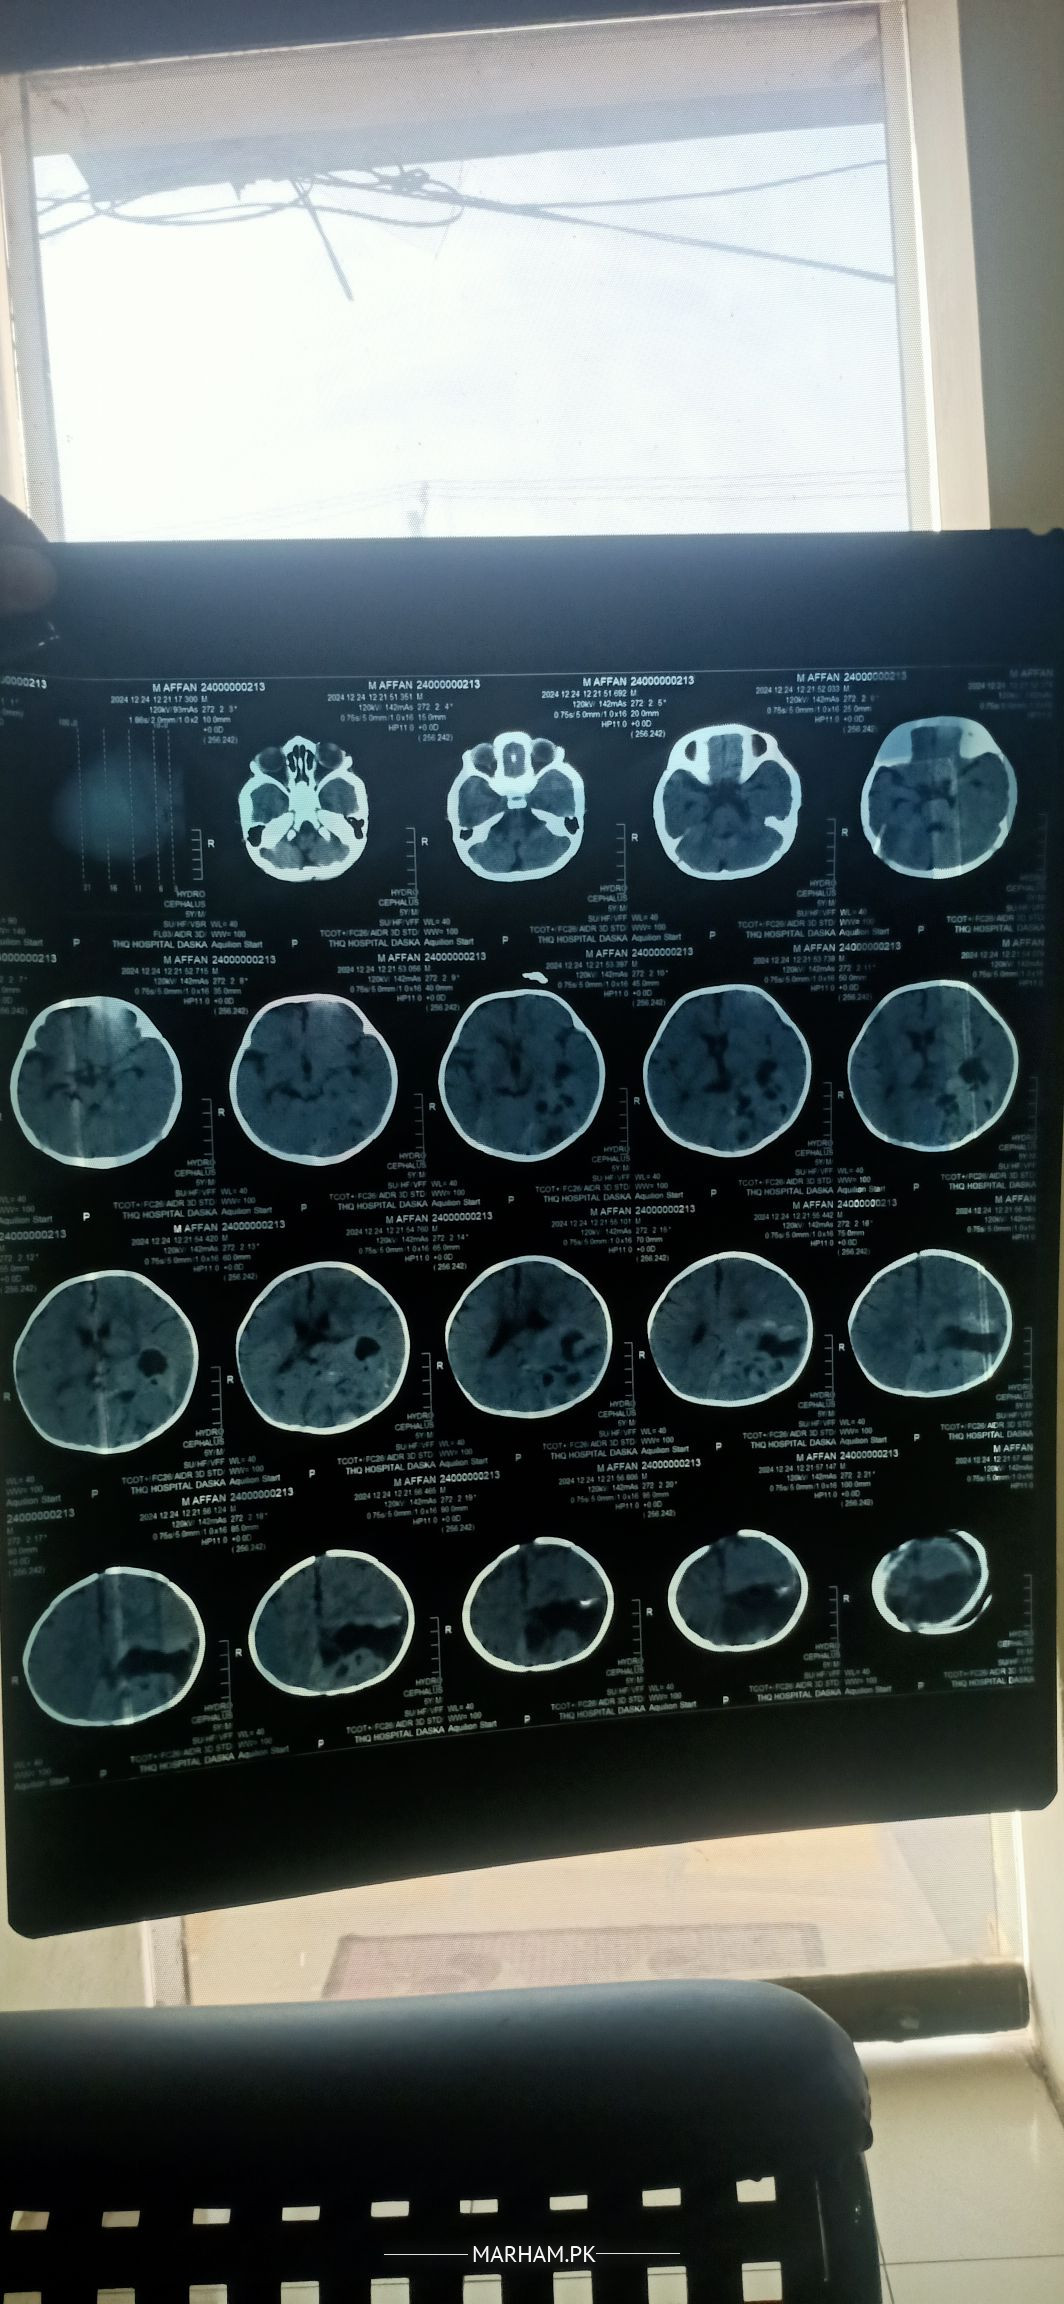

Aoa mera batija ha 5 months ka wo feed kr k vomiting kr deta ha to docter nay kaha iski CT scan krwao wo krwai to docter nay kaha ha iska koi Valve band ha lekin bacha bilkul theek ha dekhta sunta khelta move b theek krta ha bss ye masla ha kindly koi neurologist agr dekh kr kuch bta sken to plz guide krden kya krna docter nay 2 test b blood k kaha ha krwanay ko 1 triglyceride ka or 1 V4 aisa koi test ha main CT scan X-ray attached kr rha hn

Brain does not have valves, instead it consist of lobes.

valves nhn ventricles hotay hen brain men

Doctor is saying right. follow advice. Get tests and further workup. And better to consult pediatric neurologist/ pediatric neurosurgeon.